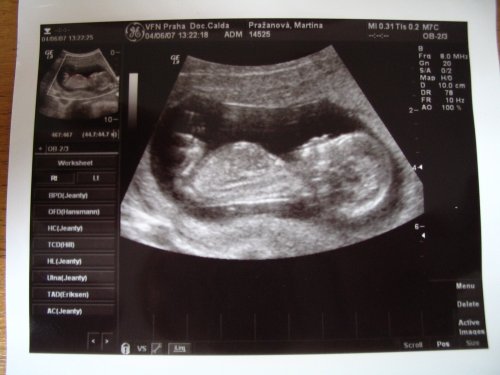

Tak poradna dopadla výborně, vše v naprostém pořádku, ťuk ťuk ťuk....a malý už váží neuvěřitelných 1.479 g (31+4.tt)